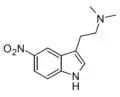

| 5-Nitro-DMT[13] | artificial | 5-NO2 | CH3 | CH3 | 5-nitro-N,N-dimethyltryptamine | 69937-13-9 |